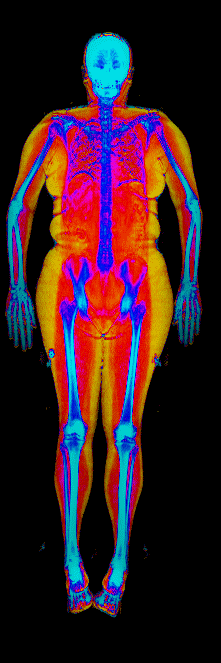

This page features real, anonymized DEXA scan images from BodyStats clients, organized by gender and body fat percentage in 5% increments. DEXA (Dual-Energy X-ray Absorptiometry) is the clinical gold standard for measuring body composition — far more accurate than scales, calipers, or visual estimates.

Each colorized scan shows the distribution of fat tissue (shown in warmer colors) and lean tissue (cooler colors) throughout the body. Compare your own DEXA scan to others in your range, or see what different body fat levels actually look like on a scan.

25 to 30% body fat

30 to 35% body fat